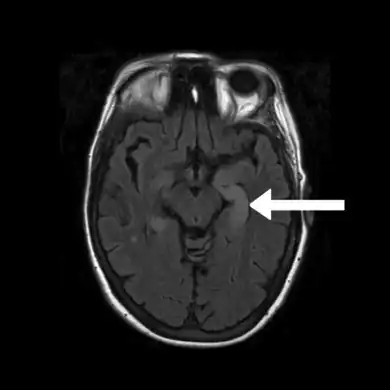

FLAIR MRI-Indicates bright signal from medial temporal lobe consistent with limbic encephalitis arrow

Neuroimaging

Brain MRI is the mainstay of initial investigation pointing to limbic lobe pathology revealing increased T2 signal involving one or both temporal lobes in most cases.[22][14]

Serial MRI in LE starts as an acute disease with uni- or bilateral swollen temporomesial structures that are hyperintense on fluid attenuation inversion recovery and T2-weighted sequences. Swelling and hyperintensity may persist over months to years, but in most cases progressive temporomesial atrophy develops.[23]